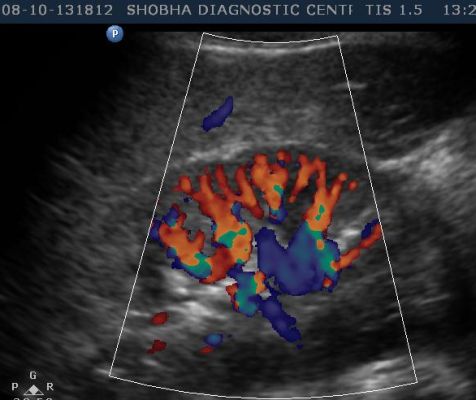

- Abdominal Doppler

- RENAL ARTERY

In color Doppler the blood circulation is assessed. It is more often done in diabetic patients, in chronic smokers who are more prone to develop blockage in their arteries, in patients who suffer from varicose vein problem.

It is non invasive test which tells you about blood circulation to any particular part of the body like upper limb, lower limb, blood supply to any tumor or swelling involving the body.